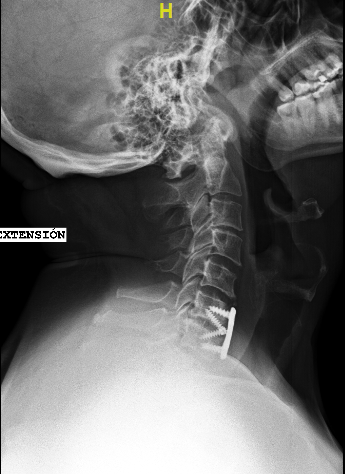

Las RX dinámicas reflejan la ausencia de fusión C6-C7